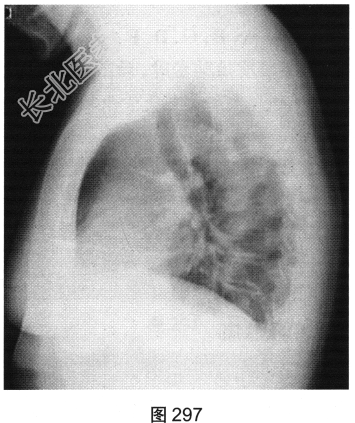

- [材料题] 患者女性,38岁,咳嗽、咳白痰10个月,伴活动后喘憋,无发热、盗汗、咯血、胸痛、胸闷、腹泻、腹胀等。胸部X线片如图296、图297所示。

- 多项选择题1.从患者的胸部X线片中可见哪些阳性征象( )

A、双肺纹理增粗

B、右肺尖高密度结节

C、右肺下野高密度斑片影

D、双侧肋膈角钝

E、双肺门增大

F、右肺下野囊状透亮影